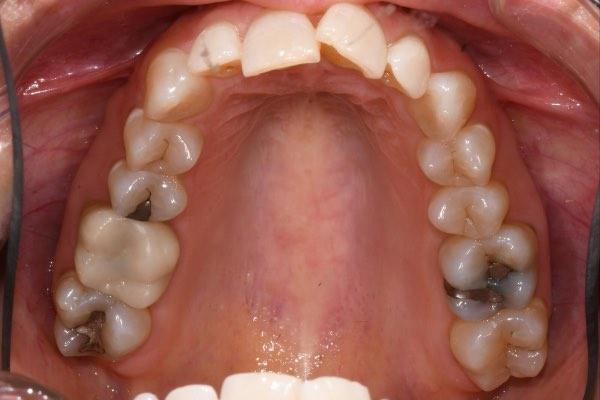

Dr. Sheila Naik and team use cutting edge technology in a state-of-the-art office to create the healthy and attractive smile every patient deserves. With biomimetic dentistry in mind, we reduce the need for invasive treatments by always preserving as much of your natural tooth as possible. Our highly trained professionals utilize the newest advancements in evidence based dentistry to rebuild teeth and preserve their natural look and function. Please review our real patients’ before and after photos as examples of general and cosmetic dental transformations experienced.